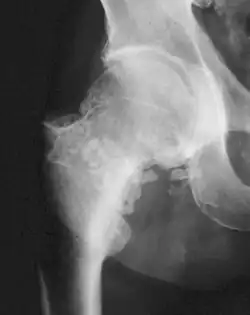

Die Synoviale Chondromatose ist eine seltene Erkrankung der Synovialis großer Gelenke. Es handelt sich um eine knorpelbildende Metaplasie (Chondromatose). Die ersten Kasuistiken stammen von Paul Friedrich Reichel, Melvin Starkey Henderson (1918) und Hugh Toland Jones (1924).[1][2][3] Die Ursache ist der Erkrankung ist unbekannt.

„Häufig“ befallen sind Knie-, Hüft-, Schulter- und Ellbogengelenk.[6] Auch das Kiefergelenk kann betroffen sein.[7][8]

Die synoviale Chondromatose ist eine radiologische Blickdiagnose. Als gefürchtete Komplikation ist die Entstehung eines sekundären Chondrosarkoms zu sehen.[9][10] In einer größeren Studie mit 53 Fällen in 30 Jahren wurden drei Chondrosarkome diagnostiziert.[4]